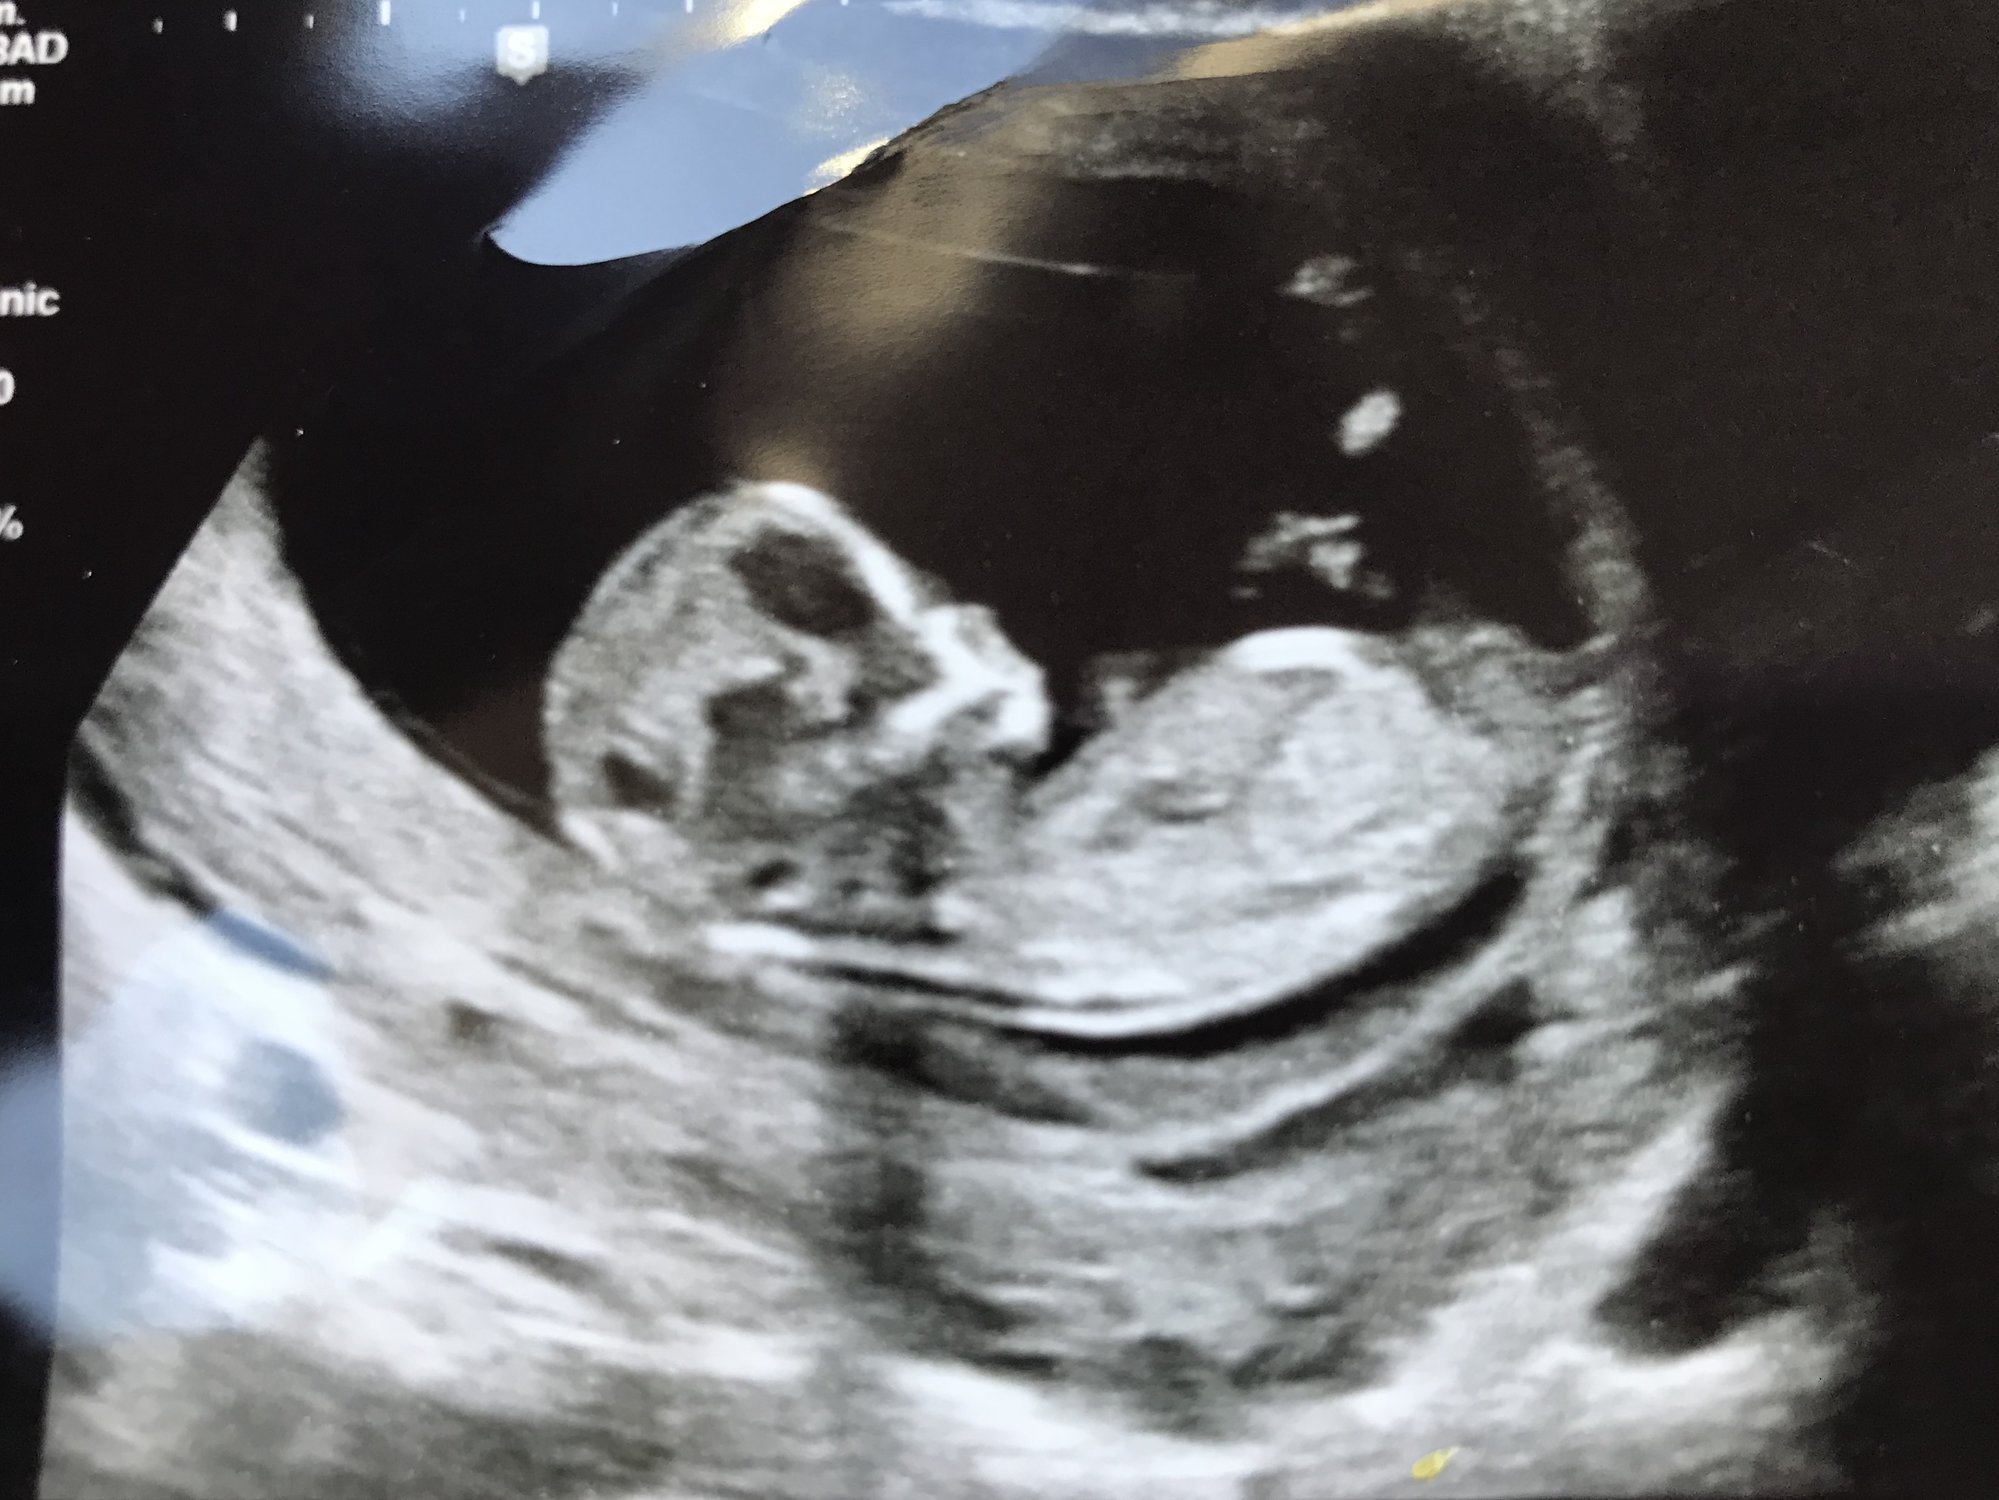

<div class="QuoteText">hi this is my 12 week sonogram , can you tell if boy or girl ? Thanks in advance <img src="https://us.v-cdn.net/5020794/uploads/editor/64/kpiruaif7oam.jpeg" alt=""><img src="https://us.v-cdn.net/5020794/uploads/editor/00/5lvbiiiz5ys2.jpeg" alt=""></div>